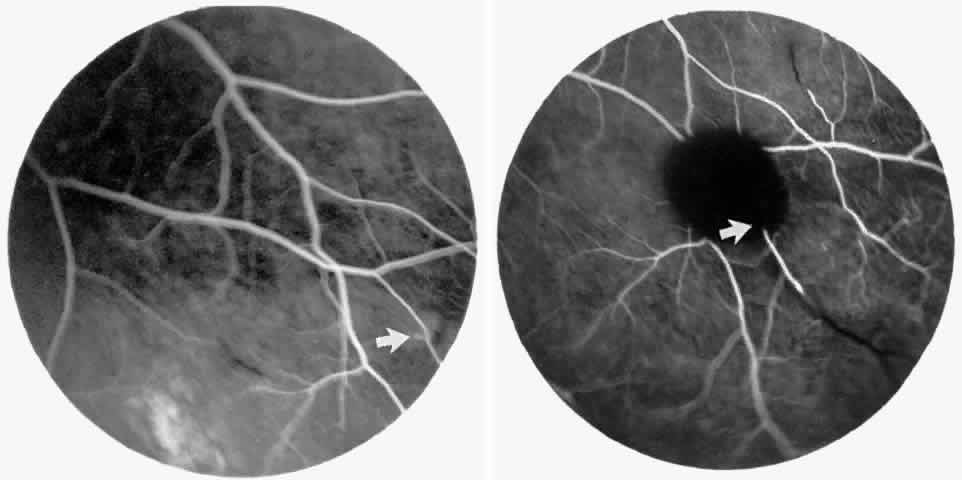

Other macular and perimacular changes include microaneurysm-like dots, dark and enlarged segments of arterioles, hairpin-shaped venular loops, pathologic avascular zones, and widening and irregularities of the foveal avascular zone (Figs. 11 and 12). In the Jamaican cohort study evaluating children with homozygous sickle cell anemia and SC disease between the ages of 5.0 and 7.5 years of age, no pathologic avascular zones could be identified despite a high incidence of peripheral vascular closure.31 In evaluating patients with homozygous sickle cell anemia, no relationship between ISC counts and macular abnormalities or visual acuity could be found.101 Using fluorescein angiography, investigators have found the foveal avascular zone to be significantly larger in eyes with clinical evidence of sickle cell maculopathy as compared with normal eyes and eyes without clinical evidence of sickle cell maculopathy.102–104

Fig. 11. A. A 40-year-old woman with homozygous sickle cell anemia. A fluorescein angiogram demonstrates multiple microaneurysm-like dots with fluorescein leakage, hairpin loop (arrowhead), pathologic avascular zones (arrows), and a widened, irregular foveal avascular zone (FAZ). B. Fluorescein angiogram of a 30-year-old woman with homozygous sickle cell anemia demonstrates multiple microaneurysm-like dots and a widened, irregular FAZ.

Fig. 12. A. Fluorescein angiogram of the left eye of a 40-year-old man with homozygous sickle cell anemia, demonstrating an irregular foveal avascular zone (FAZ), hairpin loops, and loss of the temporal capillary network. B. Fluorescein angiogram of the right macula of a 38-year-old woman with homozygous sickle cell anemia, showing an abnormal FAZ, hairpin loop (arrowhead), and pathologic avascular zones (arrows).

Careful examination by fluorescein angiography, looking for areas of capillary dropout and other capillary abnormalities, is often necessary to identify the macular changes. These changes may be transient, and the macula may appear normal on subsequent fluorescein angiograms (Fig. 13). Although fluorescein angiography may or may not demonstrate reperfusion of a previously occluded capillary bed, a loss of the inner retinal layers results in an ophthalmoscopic focal concavity with an abnormal reflex (retinal depression sign) (see Fig. 8E).105,106 These changes are usually permanent. The retinal depression sign is not pathognomonic of sickle cell disease and may be seen with other arteriolar occlusive diseases, such as embolic retinopathy, vasculitis, and hypertension.

Fig. 13. A. A 32-year-old man with homozygous sickle cell anemia and proliferative sickle retinopathy. A fluorescein angiogram shows temporal occlusions and a pathologic avascular zone (PAZ) temporal to the foveal avascular zone. B. Seven years later, there is filling of the previously noted PAZ.